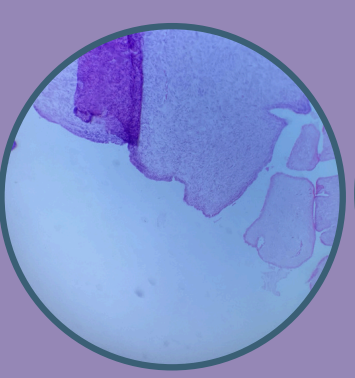

Carcinoma Papilar de Tiroides Metastásico a Ganglio Linfático:

Núcleos Orphan Anni

Presencia de proyecciones papilares

Células tumorales infiltrando el tejido del ganglio linfático

Carcinoma Papilar de Tiroides Metastásico a Ganglio Linfático